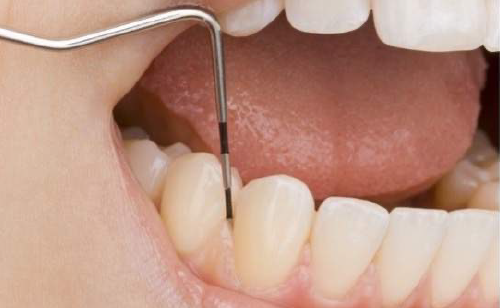

歯肉炎や歯周病になっていないか検査をします。歯と歯茎の間を触って確認し記録していきます。

歯肉炎・歯周病を診るための検査です。定期検診では、歯周病の治療にて炎症が落ち着いた場所の経過を診たり、新しく炎症を起こしていないか診ていきます。